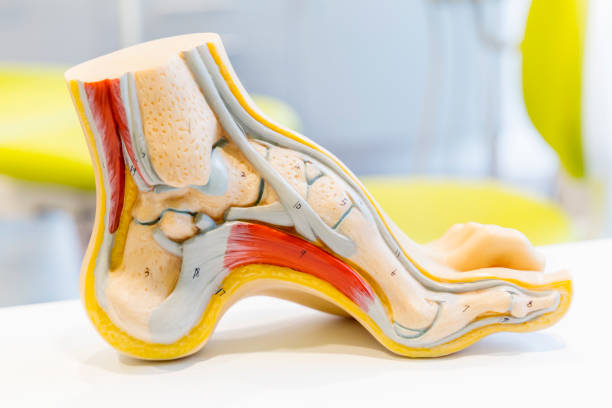

발뒤꿈치가 아픈 이유 첫 번째는 족저근막염입니다. 족저근막은 발뒤꿈치 뼈에서 시작하여 발바닥 앞쪽으로 연결되는 두껍고 강한 섬유질 띠입니다. 족저근막은 우리 몸의 중요한 역할을 하는데 아치 모양의 모양새는 우리 몸의 체중을 흡수하기 때문에 걷는 데 중요한 역할을 할 수 있습니다. 족저근막염은 이러한 족저근막에 반복되는 충격으로 근막을 둘러싸고 있는 콜라겐이 변성하면서 염증이 생긴 것을 의미합니다.

발뒤꿈치가 아픈 이유 세 번째는 점액낭염입니다. 점액낭은 아킬레스건의 움직임을 부드럽게 해주는데 이 역시 반복된 충격을 가하기 때문에 발뒤꿈치에 통증이 생길 수 있습니다. 다만 아킬레스건과 다르게 평소에도 통증이 지속되기 때문에 지속적인 관리를 해야합니다.